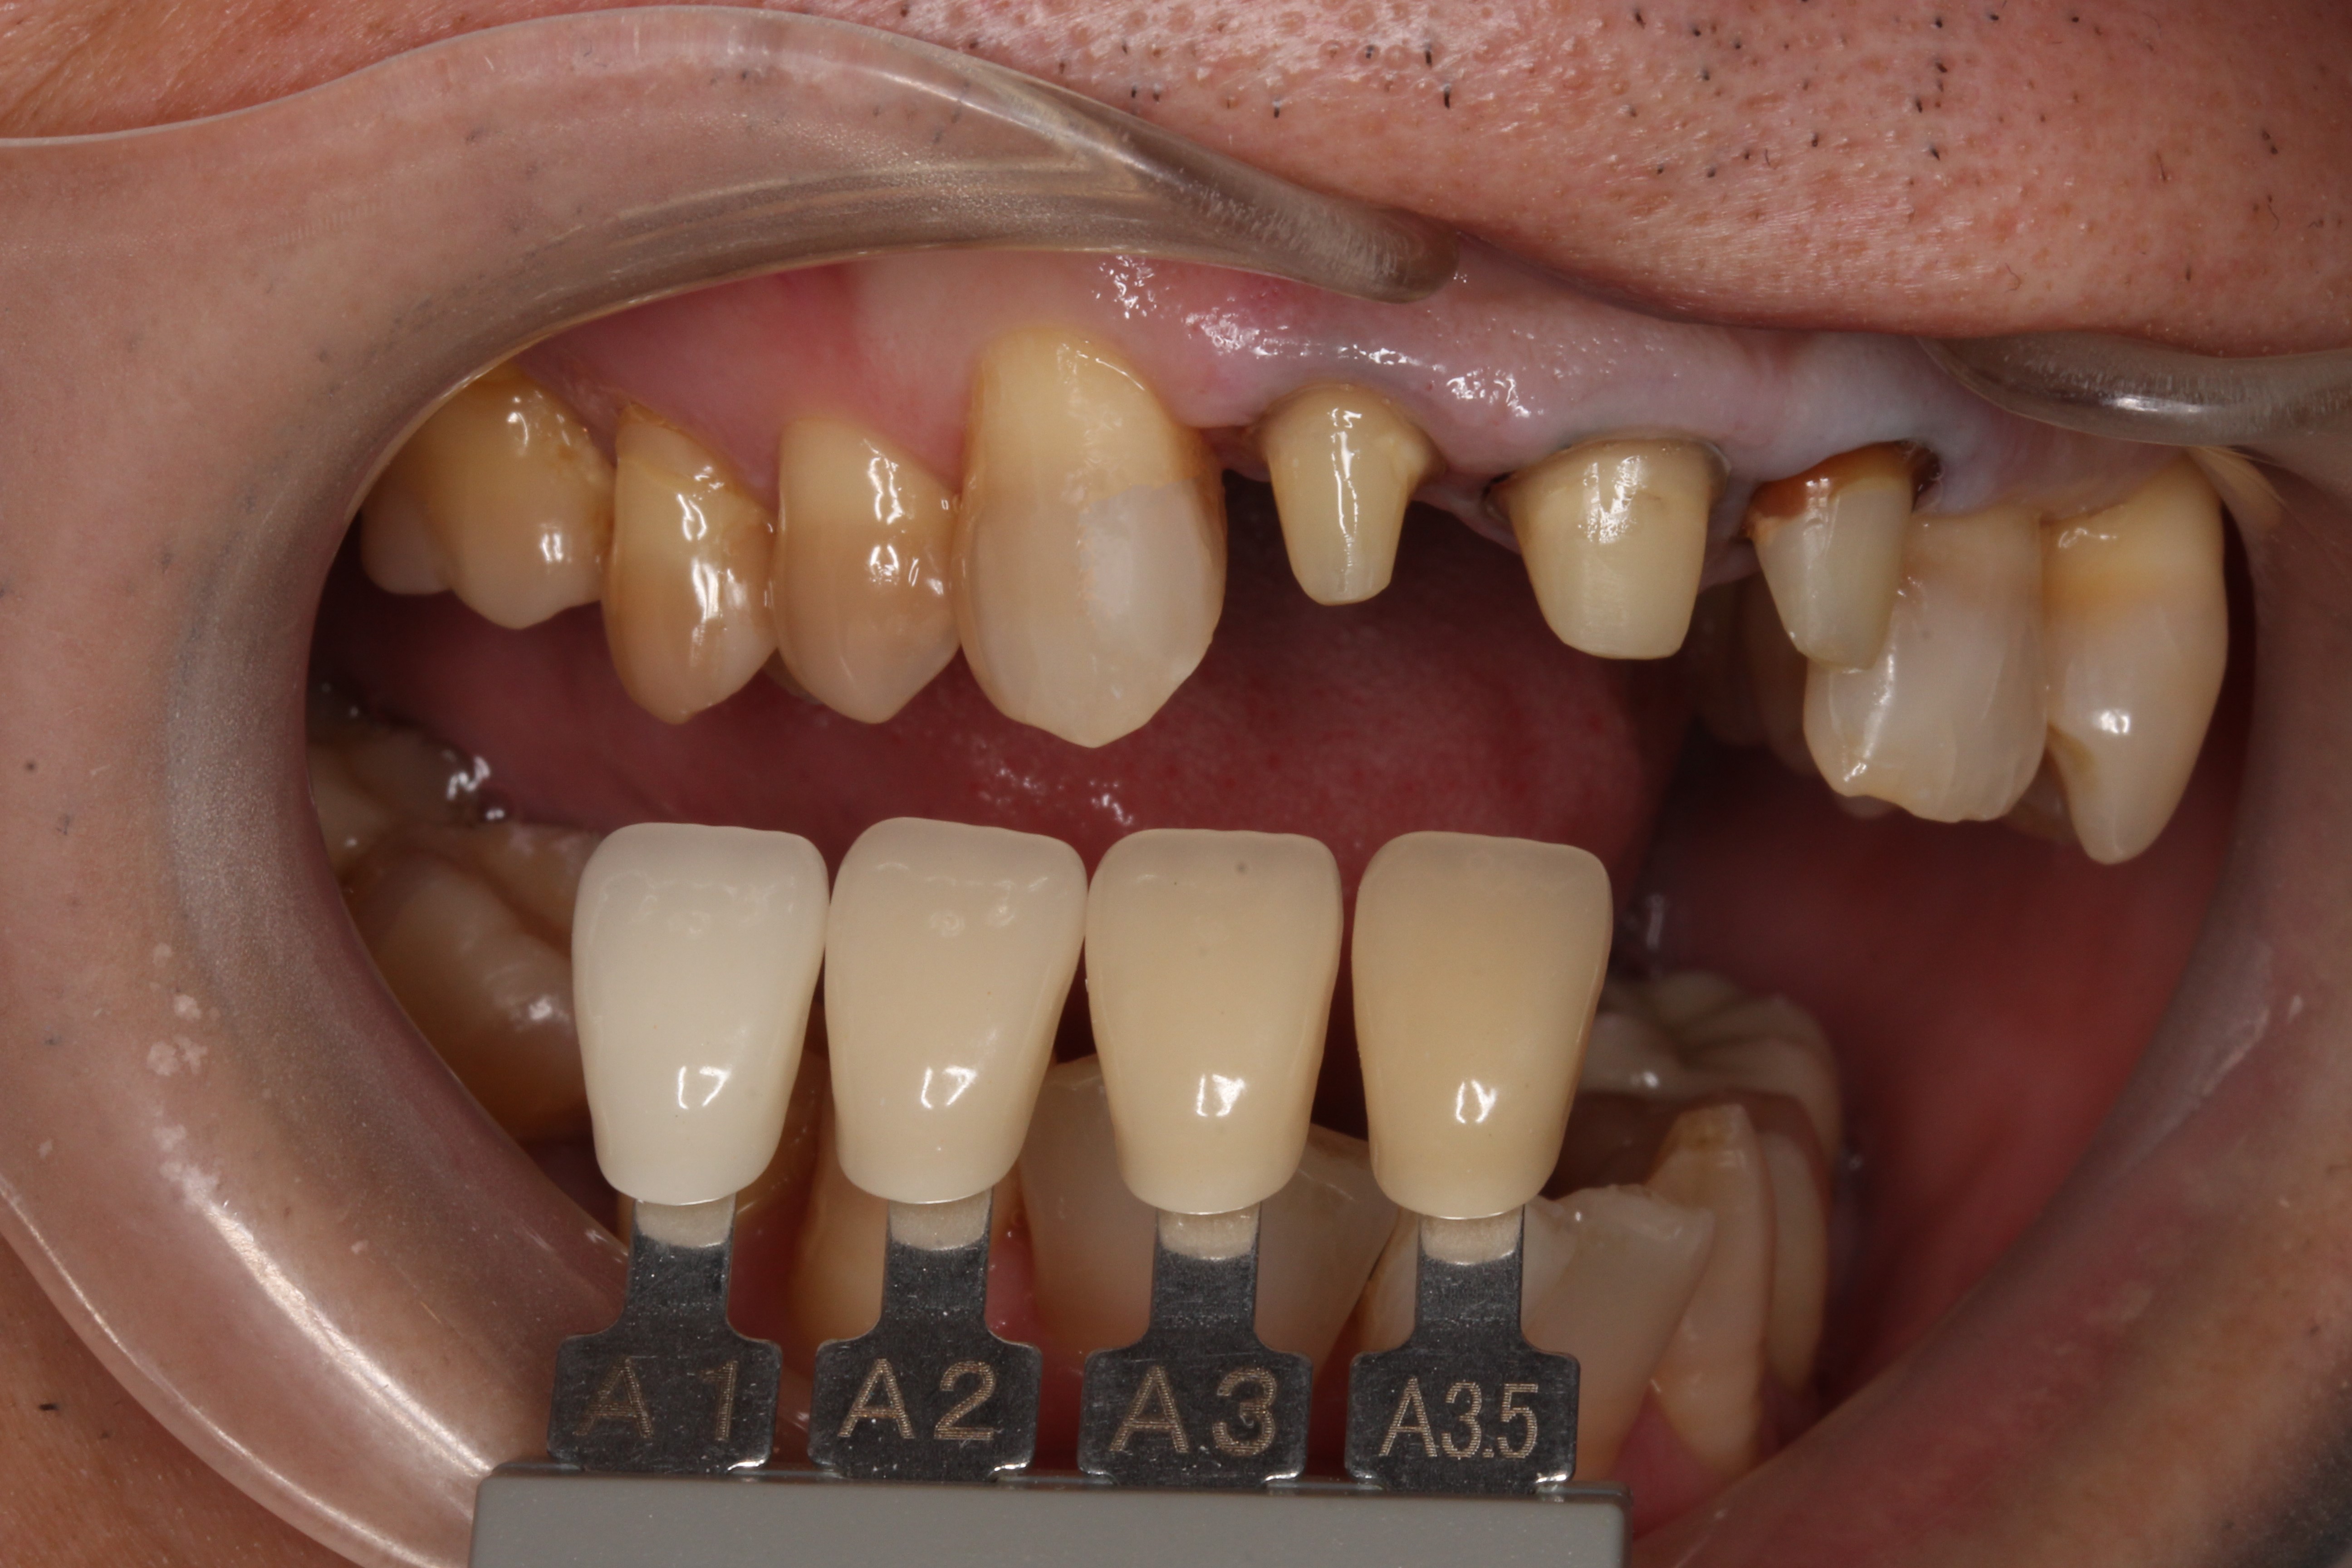

しっかりと根を清掃し、今度はファイバーコアと呼ばれるグラスファイバー製の土台を立てます。

そして、歯の色を記録。

歯科技工士に、その方に合った自然な歯を製作してもらいます。

そして出来上がったセラミッククラウン。今度は1本ずつ単独です。

歯のグラデーションや色調を合わせ製作してもらいます。

ジルコニアセラミッククラウンといって、

ベースをジルコニアとよばれる材料(人工ダイヤモンド材料)

表面がセラミックで色調を合わせています。